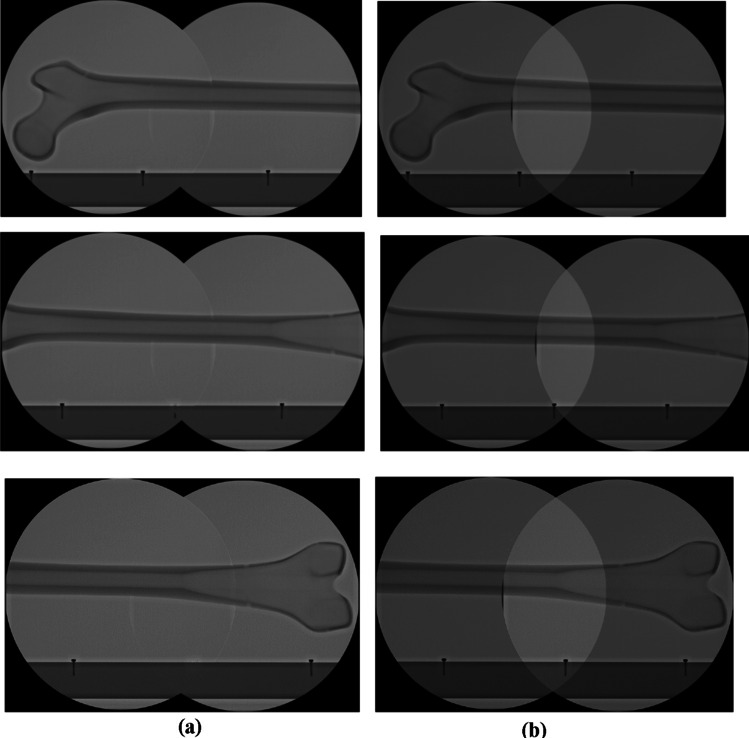

The second experiment involved stitching an actual X-ray image from the C-arm. The human femur phantom and the caprine tibia of a cadaver used for the experiment are shown in Fig. 9. To emulate the clinical configuration, an ex-vivo experiment with the caprine tibia was also conducted. Four X-ray images of the human femur and three X-ray images of the caprine tibia were acquired by the C-arm, as shown in Fig. 10. As in previous experiments, SURF, SIFT, ORB, BRISK, KAZE, the hybrid method, and the proposed method were used, and the resulting images are shown in Fig. 11. Based on the results, all of the methods except for the proposed method failed to stitch the X-ray images. Thus, this experiment confirmed the superiority of the proposed method for X-ray image stitching.

Fig. 10.

Test images for the experiment. X-ray images of (a) the human femur phantom and (b) caprine tibia cadaver

Fig. 11.

Results of the X-ray images of the (a) human femur phantom and (b) caprine tibia cadaver